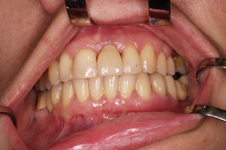

V případě chybění většího počtu zubů v postranních úsecích čelistí je možné ošetření pomocí implantátů, které nahradí ošetření pomocí snímacích náhrad kotvených na zbývajících zubech nebo patře.

Protetické řešení může být pomocí můstku, který je kotvený na implantátech nebo pomocí jednotlivých korunek na implantátech.

V zásadě je možné do těchto můstků zařadit i přirozené zuby, zejména pokud je potřeba tyto zuby ošetřit proteticky

- korunkami. Korunky nebo můstky mohou být na implantáty nacementovány nebo přišroubovány.

Zdravé zuby zůstanou zachovány a přitom náhrady jsou pevné, jako na vlastních zubech

S pomocí zubních implantátů můžeme díky různým kotevním systémům (třmeny, kulové hlavy, Locatory) zajistit stabilitu a držení protézy nebo při použití většího počtu implantátů zhotovit pevné náhrady – můstky nalepené nebo našroubované na pevno na implantáty.

S těmito typy náhrad můžeme dosáhnout perfektní funkci, výbornou estetiku, fonetiku a současně zajistit u pacienta možnost dobré hygienickou péče a čištění, která je pro životnost implantátů velice důležitá.